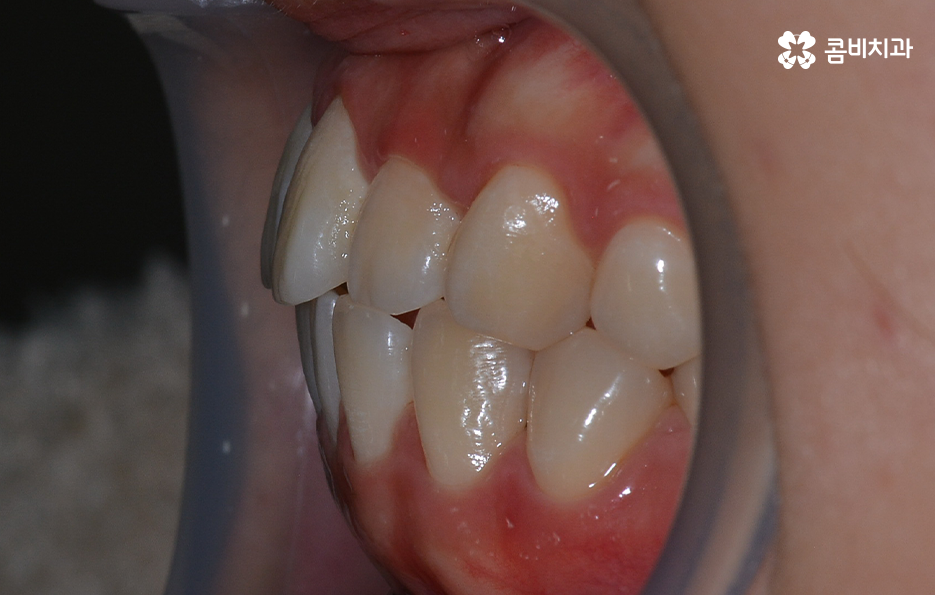

환자 개개인의 치아 상태 및 골격, 얼굴형 등의 상태가 모두 다르기 때문에 돌출입의 경우 무조건 돌출입발치교정 만이 효과가 좋다고 말씀드리긴 어렵고 돌출입이 심하지 않은 경우에는 어금니를 후방 이동시키는 것으로 치료가 가능한 경우도 있어요

물론 어금니 후방 이동의 경우에는 사랑니를 발치해야 할 수 있고, 치료 기간이 길어질 수 있음을 말씀드리며, 치아교정의 원리로 볼 때 치아의 이동 공간이 있어야 치열을 가지런하게 펴는 등의 치료가 가능하다는 점이 포인트라 할 거예요

보편적으로 돌출입발치교정 통해 치료가 진행되면 돌출입이 개선되는 경우가 대부분이지만 앞니의 각도나 턱뼈와의 상관관계 등을 고려할 때 치아교정 만으로는 치료의 만족도가 높지 않은 경우도 있는데요. 이 경우 외과 수술이 동반되어야 할 수 있습니다.

치아교정을 잘하기 위해서는 자신의 구강 구조 및 얼굴형 등을 종합적으로 정밀 검진하여 경험 많은 교정 전문의와 충분한 상담의 필요하며 수많은 돌출입발치교정 사례가 존재하기에 나에게 맞는 치료 방법을 잘 아는 것이 중요하다는 것을 강조드리고 있어요